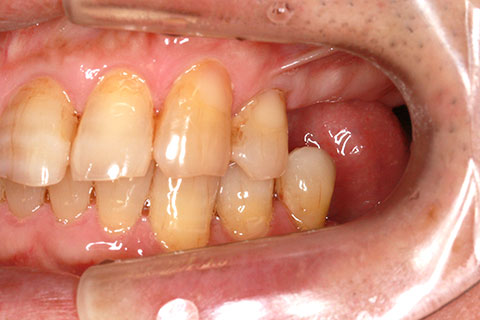

• オールセラミックの症例3

治療前

治療後

古くなった被せをジルコニアセラミックスで治療。

年齢・性別

60歳女性

治療期間

1ヶ月

抜歯

なし

治療費

35.2万円

備考

古くなった被せを新たなセラミックス冠にする。

治療内容

歯質を削除し、セラミック冠をセメント合着

施術の副作用(リスク)

知覚過敏、歯髄炎、荷重負担